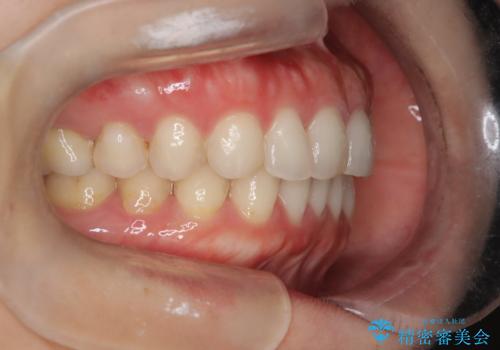

- 下顎前歯の叢生を主訴に来院されました。

臼歯関係の状態から下顎前歯一本の抜歯を行う治療計画を立て、インビザラインを使用して治療を行いました。

今回の抜歯ケースはインビザラインでも綺麗に治ります。